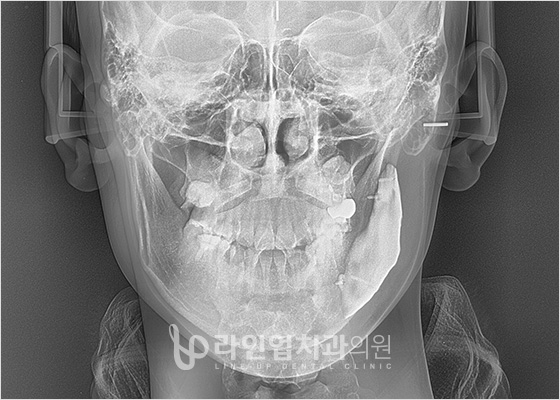

Before and After

Before

After